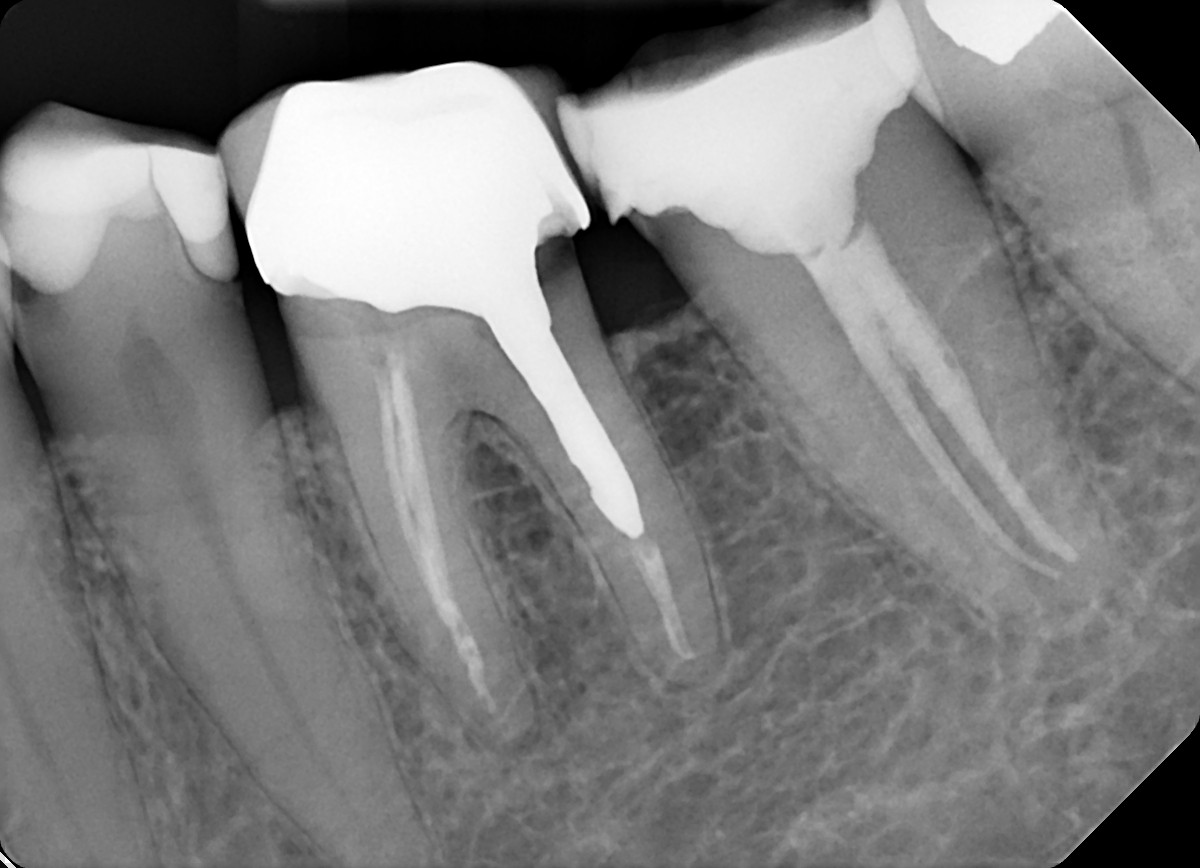

3. Evaluate the root canal treatment of tooth # 1.7?

4. Evaluate the root canal treatment of tooth # 3.6?